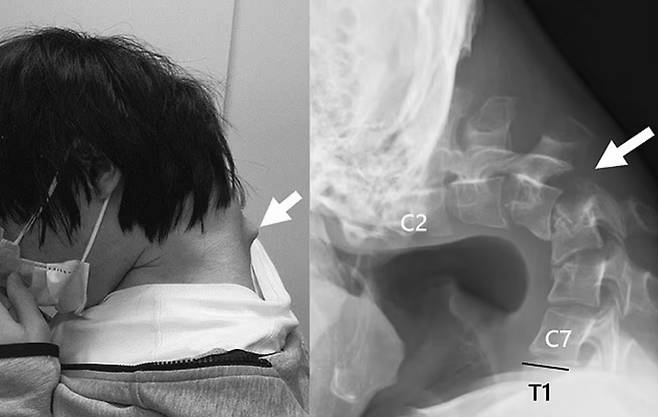

지나친 스마트폰 사용으로 목뼈가 꺾여 고개를 제대로 들 수 없게 된 20대 남성 모습이 공개됐다.

18일 영국 데일리메일에 따르면 최근 일본 의료진은 한 학술지를 통해 스마트폰 과다 사용으로 목뼈가 심하게 손상된 25세 남성 사례를 소개했다.

해당 남성은 약 6개월간 극심한 목 통증을 겪다 병원을 찾았다. 남성 목뼈는 심하게 뒤로 젖혀져 있는 상태로 일부는 비정상적으로 이탈한 상태였다.

그 결과 스스로 고개를 들 수 없었고 음식물 삼키기조차 힘들어 식사량이 현저히 줄면서 체중이 급격히 준 상태였다.

의료진은 이 남성이 수년간 바닥을 보며 스마트폰 게임을 하면서 경추에 비정상적인 하중이 지속해서 가해진 결과라고 판단했다.

특히 목을 깊이 숙인 상태에서 장시간 스마트폰을 사용하는 습관이 원인이 됐다고 의료진은 분석했다.